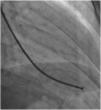

Afterwards, a 7.5 Fr (external diameter 6 Fr) Asahi Eaucath sheathless guide catheter was advanced over a standard 0.035” J wire to the ascending aorta. An MP 1 or JR 3.5/4 curve was used according to operator choice. The dilator was removed and a 5 Fr pigtail catheter was then used inside the 7.5 Fr for crossing the aortic valve and safely”landing” in the left ventricle. The guide catheter was advanced over the pigtail, which was then removed, and placed in the mid-cavity of the left ventricle. The catheter was connected to the pressure system, initial LV pressure was recorded and a minimal amount of contrast was injected (Figure 1). A 5.5 Fr Cordis 104 cm or 5.4 Fr Maslanka 120 cm bioptome was advanced and the myocardial wall was sampled (Figure 2). Back-bleed from the catheter and, if necessary, aspiration, were then performed to ensure no air bubbles were in the system. These steps were then repeated several times until the desired number of samples was obtained – a minimum of five – of which at least one was frozen for further analysis, if necessary.